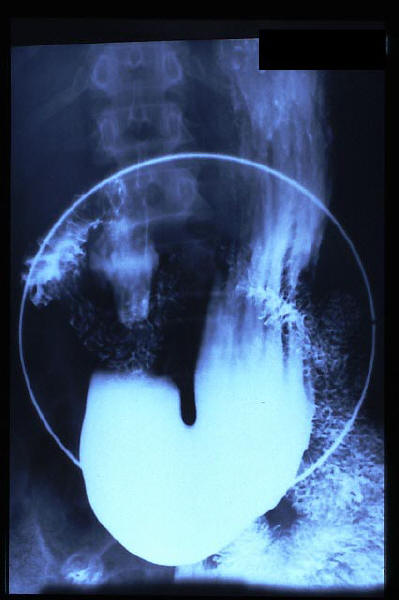

Hernia de hiato gigante.

Hernia de hiato por deslizamiento al TGED.

Hernia de hiato por deslizamiento al TEGD.